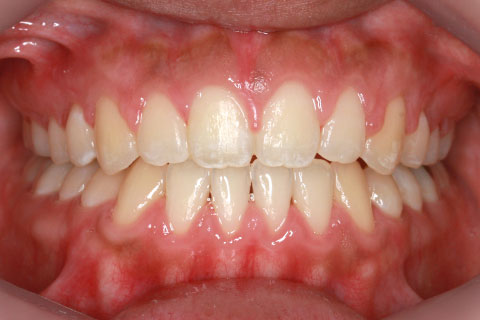

治療後

下顎骨骨切り術を併用した外科的矯正治療

治療内容

マルチブラケット法+下顎セットバック